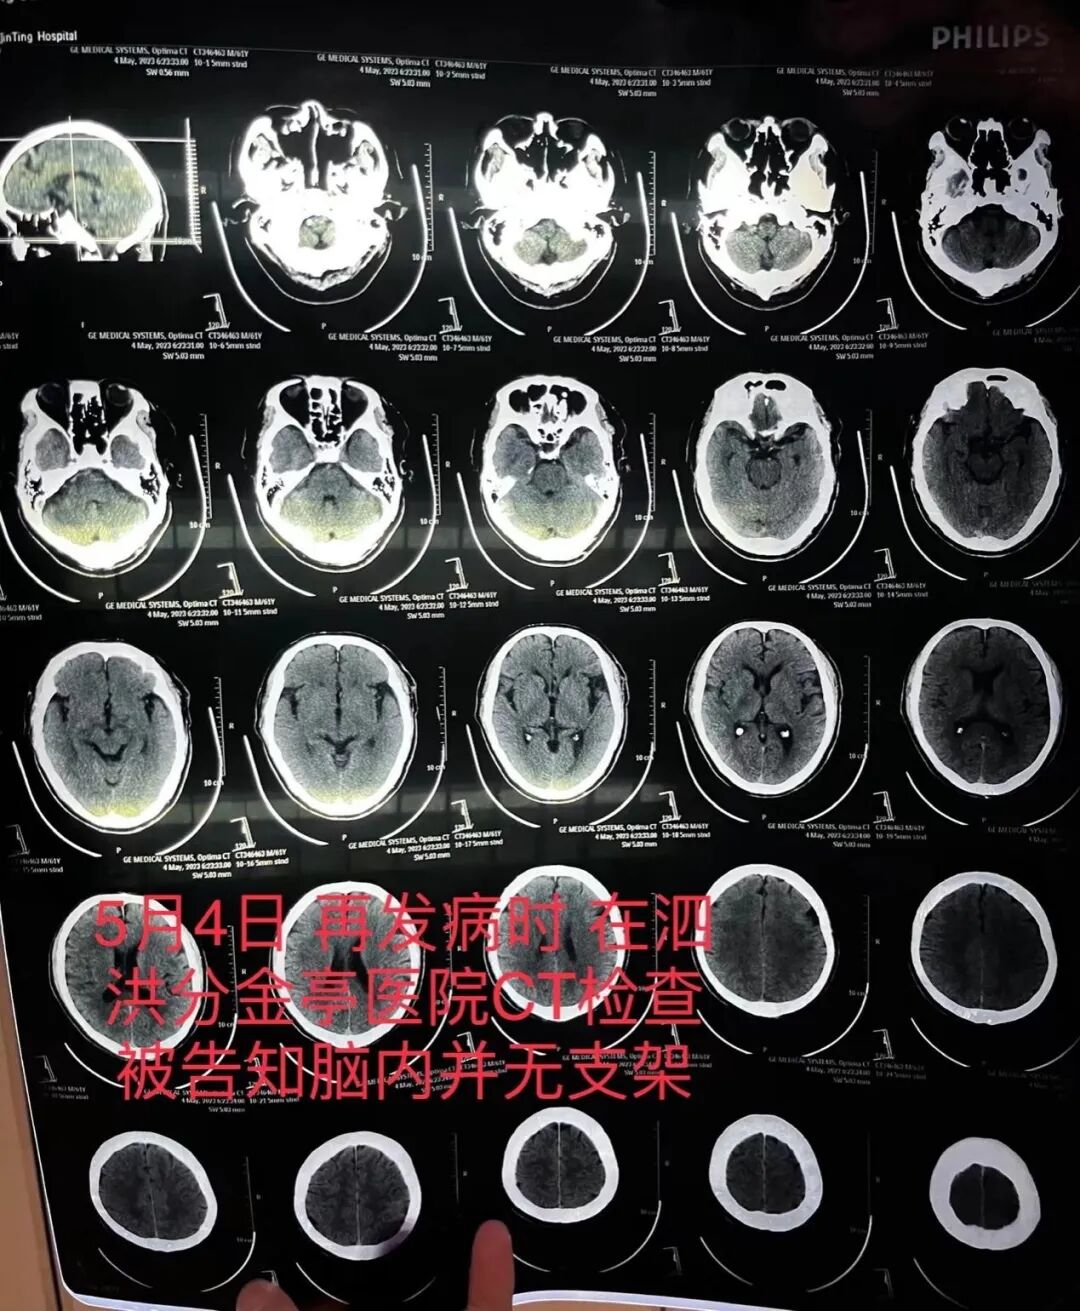

6月10日,澎湃新闻刊发《宿迁一患者因脑梗去世,医生承认此前未成功植入脑血管支架并隐瞒》一文,受到广泛关注,其背后的法律问题,也引发网友热议。 多位关注医疗纠纷的律师向澎湃新闻分析表示,目前单凭患者家属提供的住院病历记录、涉事医生的电话录音等内容,无法判断医院医疗行为是否存在过失,须进行鉴定。不过,涉事操刀医生的隐瞒行为,已经违反了《民法典》和《医师法》等相关法律和医师职业道德规范。若经过当地卫健委调查,证实其行为与患者死亡存在因果关系,性质严重的,涉事医生会被吊销行医执照,还可能因涉嫌“医疗事故罪”,被追究相关刑事责任。 还有律师指出,医务人员为患者治疗是一种“职务行为”,当发生医疗纠纷后,若存在医疗责任,则院方是赔偿责任主体。 9日晚,逝者的儿子朱先生告诉澎湃新闻,老人已下葬,但其并未告知是否已进行尸检。对此,有律师表示,由于涉事医院的手术记录等病历涉嫌伪造,司法鉴定已存在一定难度,若老人未能接受尸检,死因难以明确。 此外,针对支架未能植入却被收费的情况,接受采访的律师均认为,从现有证据来看,该笔费用应当由院方承担。有律师还提出,如果支架费用通过医保结算,涉事医院可能存在骗保嫌疑。 朱老汉在泗洪县分金亭医院的CT检查报告,显示颅内并无支架。朱先生 供图 今年4月6日,62岁的朱老汉在江苏省宿迁市第一人民医院神经内科接受经皮基底动脉支架植入术,该医院神经内科副主任医师齐某为主刀医生,术后告知家属手术成功。 朱先生提供的病程记录和手术记录均显示,手术过程中,齐某将一枚Neuroform Atlas 4.5/21支架系统,输送至病变狭窄段释放。记录中多次提到,血管狭窄问题已在手术中得到改善。 4月10日,朱老汉出院,病情稳定好转,住院医疗费用合计12万余元,部分自费。但还不到一个月,5月4日,朱老汉突发严重脑梗,被送至江苏省宿迁市泗洪县分金亭医院抢救。该院的CT血管造影显示,其颅内段部分动脉已严重堵闭,同时,并未发现植有支架。朱老汉随后被家人转入宿迁市第一人民医院,曾作为主刀医生的齐某此时承认,之前未能在患者颅内血管成功植入支架。 得知真相后,朱先生一家连夜将朱老汉转送至南京鼓楼医院。5月10日,朱老汉在该院再次接受支架植入手术,但术后其颅内基底动脉已全部血栓堵闭导致大部分脑干损坏,老人已无自主意识,无法自主呼吸。6月7日中午,朱老汉不幸去世。 在抢救期间,齐某和宿迁市第一人民医院院方代表也来到鼓楼医院。朱先生提供的电话录音中,齐某承认患者颅内没有支架,也不知道支架究竟在何处。因术中见到患者血流恢复良好,他称存在“侥幸心理”,因此隐瞒了支架未能植入的情况。“说实话,我做了这么多手术,没做成的时候很少,当时这个支架没放成,我觉得很打脸,感觉有点不好看,下不了台。”齐某说。 6月10日中午,澎湃新闻致电宿迁市卫生健康委员会,未获得有效回复。江苏省宿迁市第一人民医院纪委的电话也始终无人接听。 根据现有报道内容,北京某三甲医院神经内科主任医师万医生接受“环球时报健康客户端”记者采访时表示,基底动脉介入手术风险极高。狭窄程度超过70%的重度狭窄,需要及时进行干预治疗,否则可能危及生命。治疗方法包括口服药物、介入手术等,介入手术方式包括球囊扩张、支架植入术。“无论采取哪种疗法,都需要以患者为中心,选择最适宜的疗法。介入支架手术主要由两到三名医生完成,一名医生主刀,另外一两名医生辅助,并记录手术全过程。” 万医生分析称,齐某提到支架到达基底动脉位置进不去,可能有两方面原因:一是可能与使用的支架类型、型号、长短不合适有关,导致在指定位置无法撑开;二是技术水平不足。“此时,医生应第一时间告知家属,尽早转到更有能力的医院,为患者实施手术。” 按照《医疗纠纷预防和处理条例》第二十二条,患者可以采取以下四种维权方式:(1)医患双方协商解决(2)共同委托医疗纠纷调解委员会进行调解解决争议(3)向卫生行政部门投诉,通过行政调解方式处理争议(4)向人民法院提起民事诉讼,通过司法程序解决争议。 由于未能和宿迁市第一人民医院协商一致,朱先生决定采取民事诉讼,希望追究医院和医疗人员的医疗过失责任。 多位专家指出,目前单凭患者家属提供的住院病历记录、涉事医生的电话录音等内容,无法判断医院医疗行为是否存在过失,必须先经过当地医学会或者司法鉴定机构进行鉴定。不过,涉事操刀医生的隐瞒行为,已经违反了《民法典》和《医师法》等相关法律和医师职业道德规范。若经过当地卫健委调查,证实与患者死亡存在因果关系,性质严重的,涉事医生有被吊销医师执业许可证的风险,还可能因涉嫌“医疗事故罪”,被追究相关刑事责任。 6月9日晚,朱先生称,其从院方得知齐某已被停职,其提供的一张微信聊天截图显示,齐某自称所有工作已经停摆。记者当天致电宿迁市第一人民医院纪委询问齐某被停职一事,接线工作人员称,“不方便说。” 北京大学法学院孙东东接受环球时报采访时指出,上述事件虽属医疗行业中较罕见的情况,但也暴露出相关管理问题,“本应预见不良结果可能出现,却抱着侥幸心理没有采取防范措施,放任不良结果的出现并隐瞒实情,就不仅仅是一般的医疗过失问题了。” “故意隐瞒支架的情况比较少见,但性质较为恶劣。”上海政博律所主任律师王政告诉澎湃新闻,其从业以来,只接过两起隐瞒支架植入情况的医疗纠纷案件,但终以调解的方式和解。他认为,在本起事件中,若患者家属反映的情况属实,不管医院方对医生故意隐瞒支架未能植入、伪造病历虚构手术经过等情况是否知情,当发生医疗纠纷后,若存在医疗责任,则赔偿责任主体为医院,而非医生个人。因此医院无论是否知情,负有的法律责任程度都一样,“医院应承担主责以上。” 北京中闻律师事务所冯爱国律师同样表示,因医务人员的治疗行为是一种“职务行为”,按照《民法典》第1218条,应由其所在医院代替其向患方承担责任。因此,经鉴定后,若医院医疗行为存在违反医疗卫生法律、法规、诊疗护理规范等过错,且该过错行为与患者死亡结果存在因果关系,那么,涉事医院应当依据《民法典》第1218条、第1221条和第1179条,承担相应的医疗费、护理费、住院伙食补助费、死亡赔偿金、丧葬费等费用。 北京中医药大学医药卫生法学教授邓勇补充称,若院方存在明显过错,医疗行为与患者的死亡之间存在一定的因果关系,涉事医院和医护人员的行为还违背《医师法》《医疗机构管理条例》《病历书写规范》等法律法规中对于“告知义务”等的相关规定,应受到相应的行政处罚。同时,如果认定医务人员由于严重不负责任,造成就诊人死亡或者严重损害就诊人身体健康,还会涉嫌构成“医疗事故罪”,应承担相应的刑事责任。 “不过,这个案子有可能比较难鉴定。”王政告诉澎湃新闻,患者家属虽然有其它医院的CT血管造影等证据,但只能证明事后患者颅内没有支架。而专家在后续实际司法鉴定过程中,需要对患者在涉事医院的手术记录等病历进行鉴定,但这份至关重要的病历又涉嫌造假,加上老人已入葬,如果未尸检,死因难以明确,医院可以辩称是死因不明,维权难度较大。 不过,若能证实病历造假,当地卫生监督部门会对应做出处罚,除了撰写病历的医务人员以外,科室主任、分管医务处科长、医院相关负责人均可能承担一定责任,具体需按照各地卫生监督的相关规定为准。“一般是予以罚款,性质非常恶劣的话,卫生监督部门可能会暂停涉事医生执业资格,甚至吊销医疗机构执照。”王政说。 至于涉事医生称未成功植入但已消耗的高价支架,费用究竟该由谁来承担?受访律师均认为,应当由院方承担。 根据朱先生提供的收费票据,朱老汉在宿迁市第一人民医院住院费用共计12万余元,其中,医保统筹基金支付5万余元,大病保险支付3万余元,剩余自费。各项费用中,卫生材料费近10万元,其中,Neuroform Atlas进口颅内支架一枚价格显示为47000元。 冯爱国分析称,医患双方基于合同法律关系,按照《民法典》第577条,当事人一方不履行合同义务或者履行合同义务不符合约定的,应当承担继续履行、采取补救措施或者赔偿损失等违约责任。因此,患方可依据前述规定,要求医方返还植入支架的相关医疗费用。 邓勇认为,支架植入手术的费用主要产生在手术操作以及术中耗材上,未植入支架却收取患者全部的耗材费用不合法,同时也违背了医师职业道德和诚信信用原则,费用应由医院全部承担。 此外,邓勇还特别提醒,遇到相似的医疗纠纷,患者家属首先且必须留存好证据,封存、复印全部病历,包括主观病历和客观病历。若患者死亡的,如家属对患者死亡原因有异议的,建议48小时内进行尸检,有冷冻条件的,可延长至7日内。如果已经错过时间或已经火化下葬导致无法尸检的,可以同意鉴定机构根据病历推定患者死亡原因。